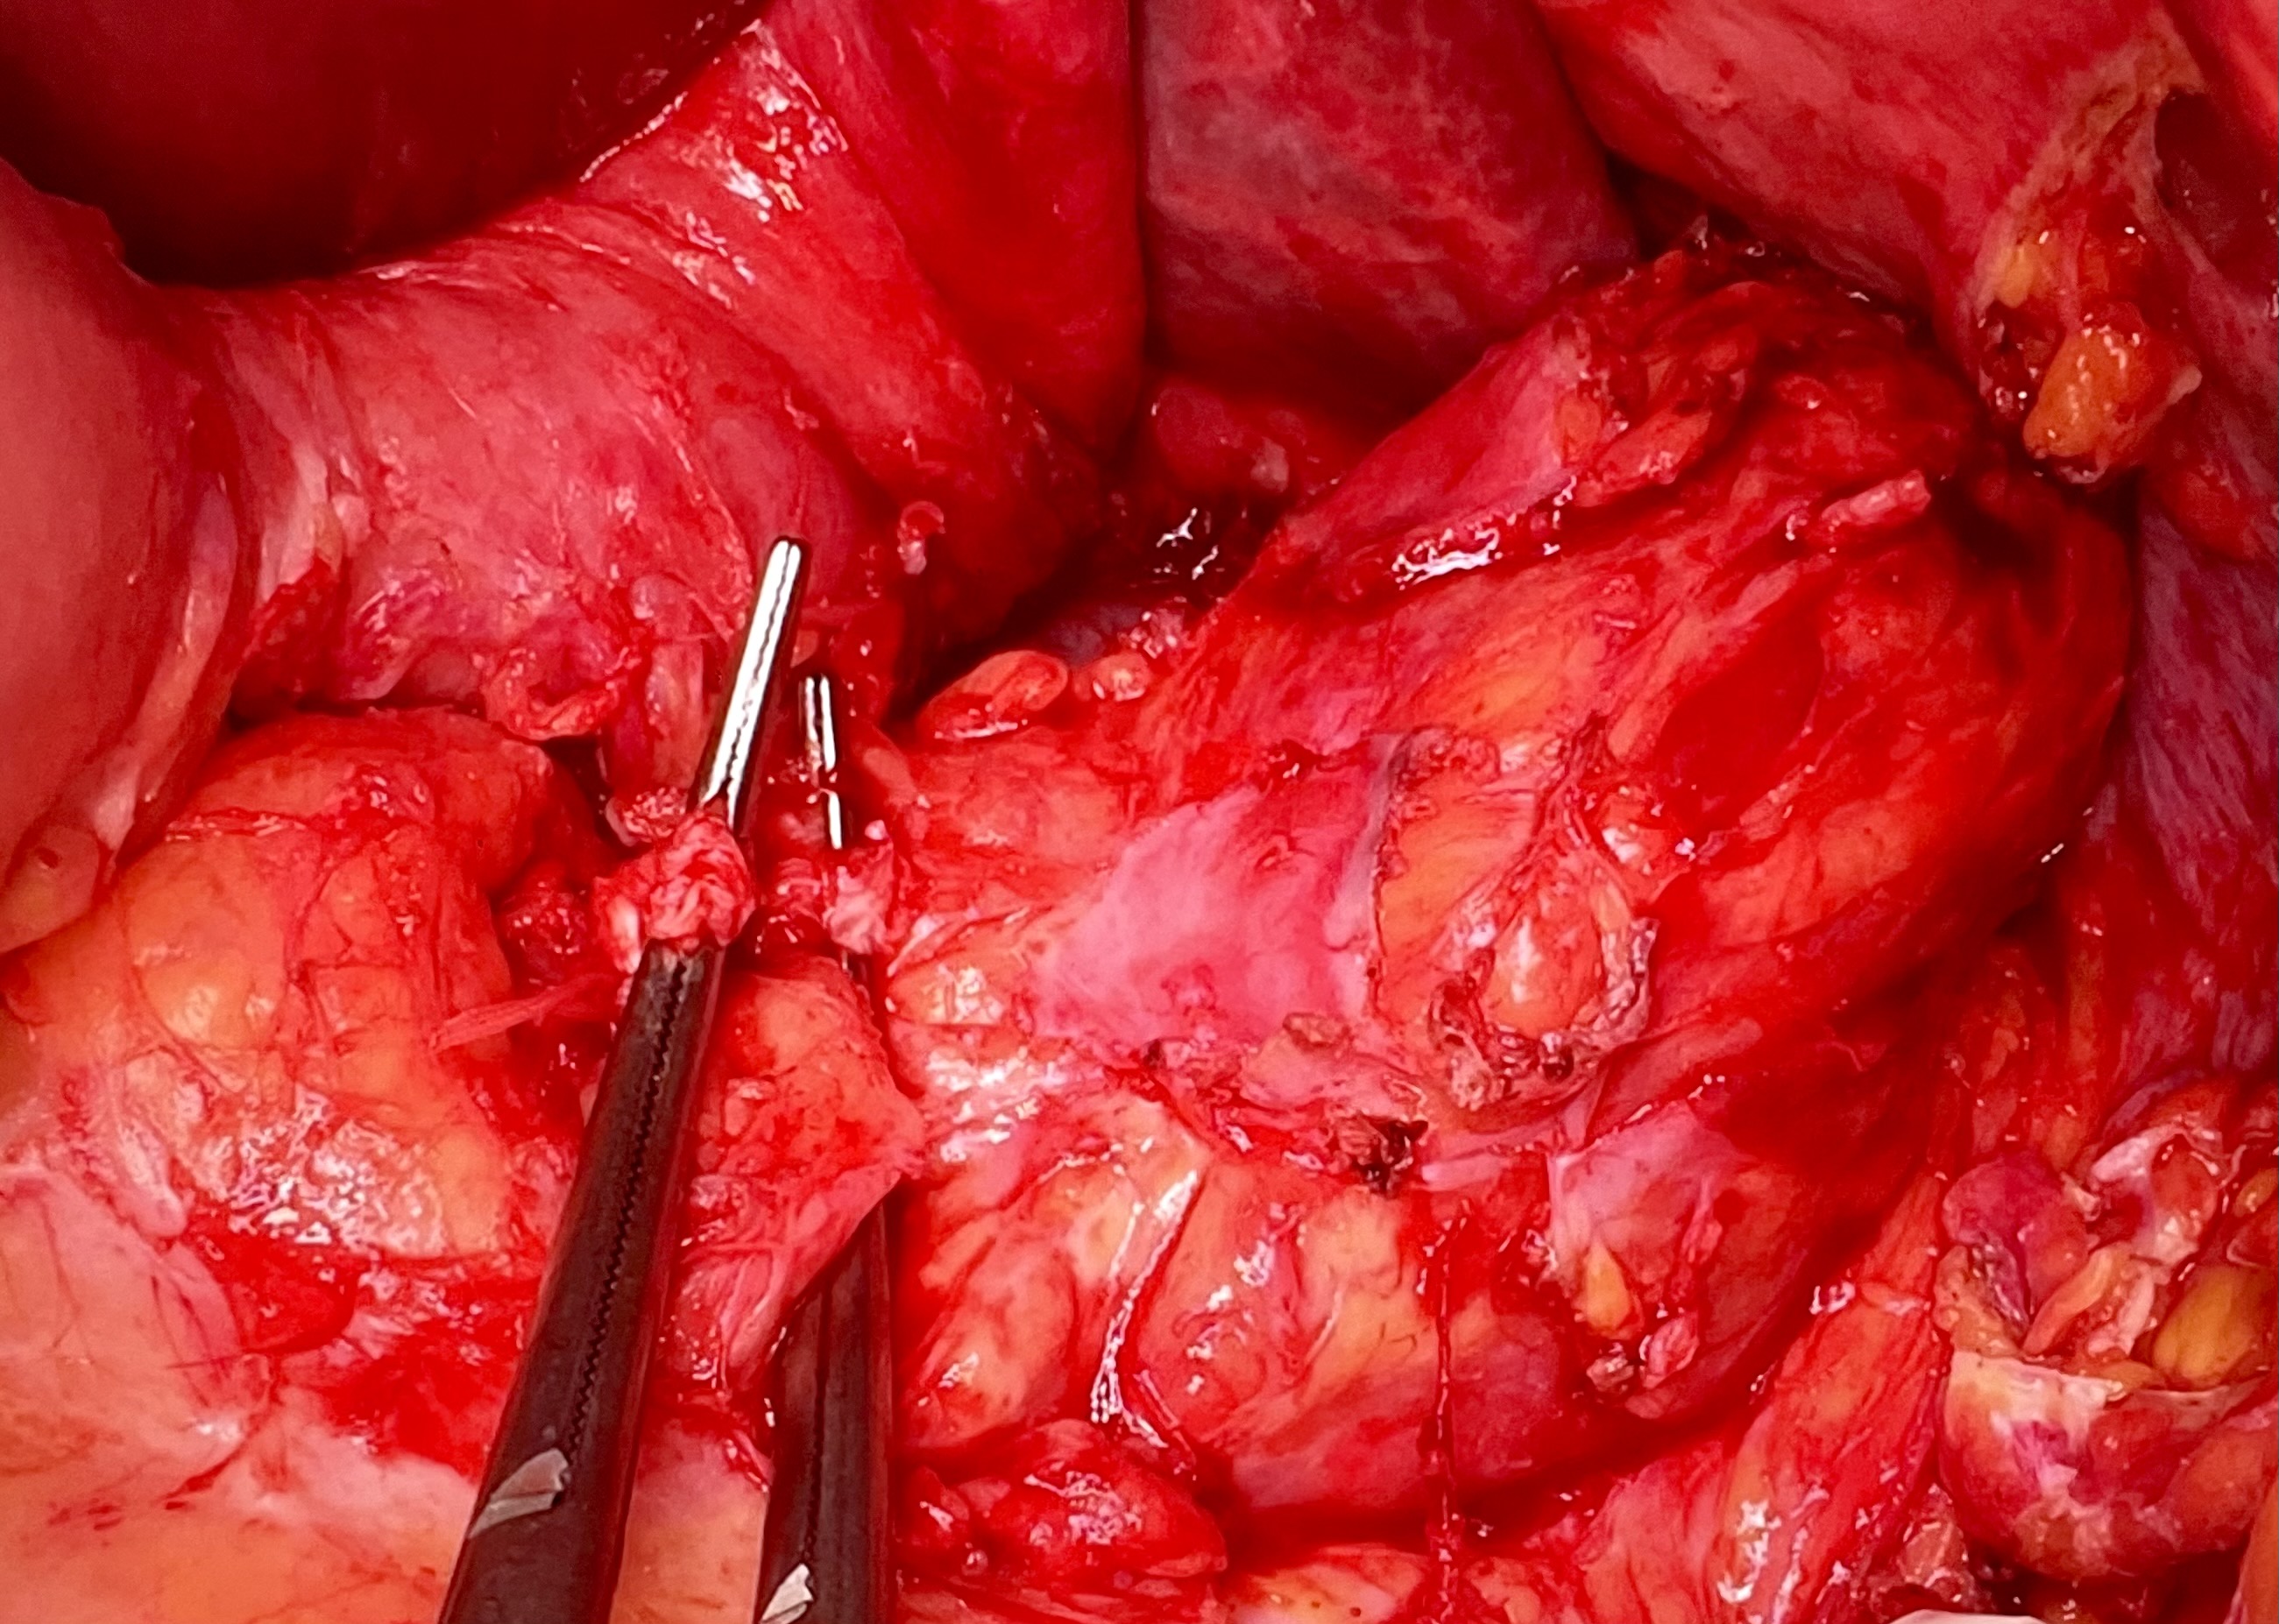

6. Выделение поджелудочной железы с конгломератом, образованным кистой, артерии-венозным соустьем и аневризмой селезеночной вены. Перевязка селезеночной артерии дистальнее окклюдера | |